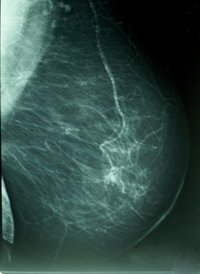

Los productos químicos o alimentos que aumentan los niveles de estrógeno durante el embarazo pueden aumentar el riesgo de cáncer en las hijas, nietas y bisnietas, según han publicado científicos de Virginia Tech y la Universidad de Georgetown en 'Nature Communications'.

En el estudio, ratas embarazadas que recibieron una dieta suplementada con estrógeno sintético o con grasa -que aumenta los niveles de estrógeno- produjeron generaciones subsiguientes que parecen estar sanas, pero que albergan un riesgo mayor de padecer cáncer de mama.

Aunque los resultados aún no han sido validados en seres humanos, el estudio muestra que el daño ambiental puede ser transmitido de una generación a la siguiente, no a través de mutaciones genéticas, sino a través de alteraciones 'epigenéticas' que influyen en cómo se decodifica la información genómica.

El Instituto Nacional del Cáncer estima que más de 226.000 mujeres y más de 2.000 hombres de más de 2.000 desarrollarán cáncer de mama en 2012, y cerca de 40.000 morirán a causa de la enfermedad.

Dos tercios de los cánceres de mama que se producen en familias no tienen una causa genética conocida, según apunta Leena Hilakivi-Clarke, profesora de Oncología en el Centro Oncológico Integral Lombardi de la Universidad de Georgetown. El estudio muestra lo que subyace al cáncer no son mutaciones genéticas, sino efectos heredados de una dieta rica en grasas y la exposición a un exceso de estrógenos durante el embarazo.